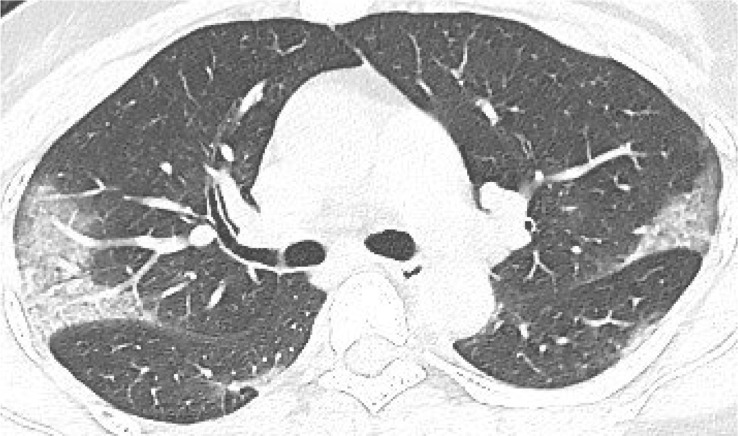

According to the guideline [9], CT examination is strongly recommended as a test for COVID-2019. According to the guidelines, the typical image of COVID-2019 presents multiple patchy ground glass opacity (GGO) along the subpleural and bronchovascular bundles in both lungs, separated by meshed or thickened lobular septa as crazy-paving pattern (54.2%) (Fig. 1, Fig. 2, Fig. 3, Fig. 4 ) and multiple patchy or large patchy consolidation in both lungs (Fig. 5 ), with thickening of interlobular septa, mainly in the middle and lower lobes (31.3%). It is consistent with the findings of Wang's [7] review of 138 cases (the CT findings of all cases involved both lungs), Huang's [1] review of 41 cases (all cases involved both lungs) and Song's [8] review of 51 cases (distribution: the lesions involved both lungs in 86% of patients, the lower lobe in 90% of patients, and the peripheral lung field in 86% of patients; density: 39% of the total number of lesions showed as GGO with reticular and/or interlobular septal thickening). Atypical images showed single lesion [10] (Fig. 6 ) and single or multiple consolidation nodules in the center of lobules, surrounded by ground glass opacities [9]. Both Song [8] and Pan [11] found that COVID-19 rarely caused mediastinal lymphadenopathy or pleural effusion.

Fig. 1.

39-year old male with dry cough for 5 days. Nucleic acid test: positive. Imaging examination: CT showed diffuse patchy GGO with crazy-paving pattern along the subpleural in both lungs.